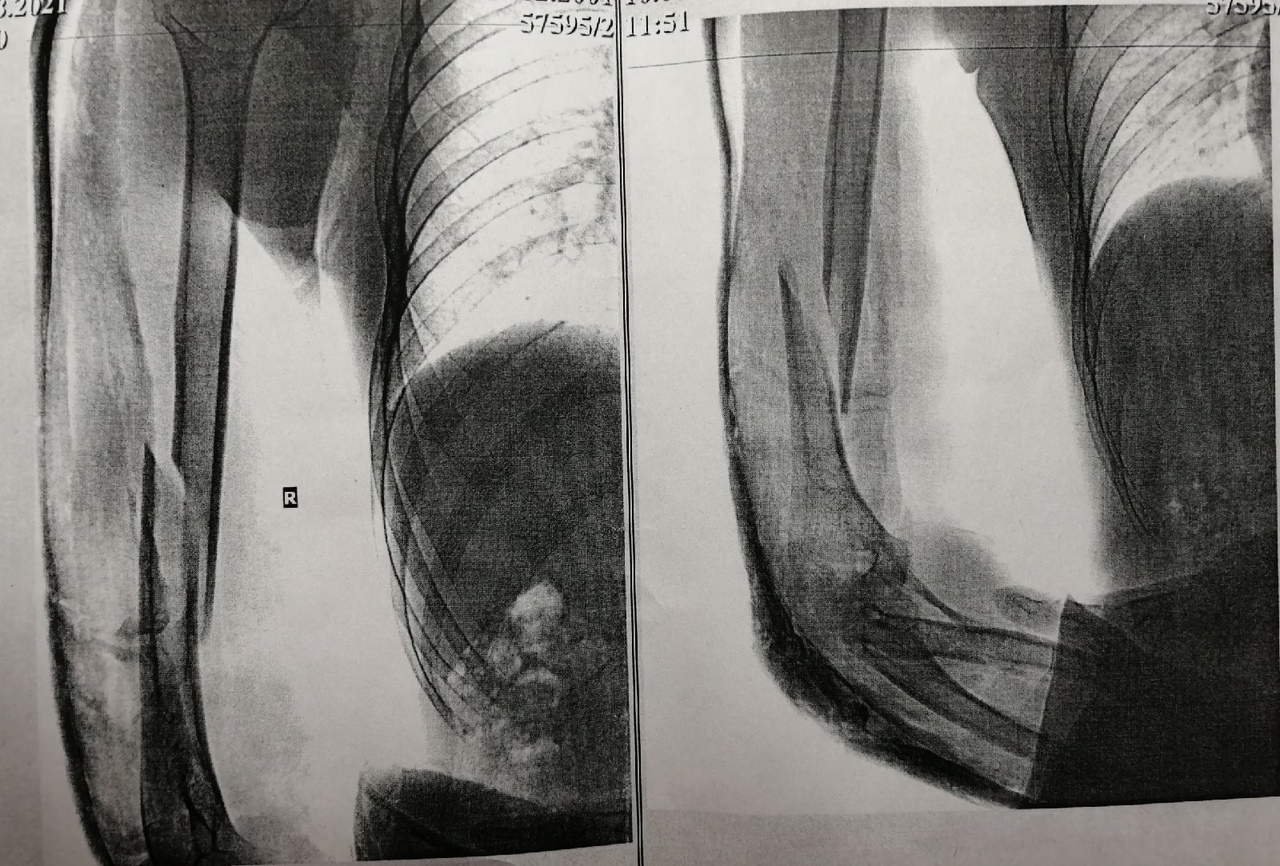

Проверял прочность костей после происшествия, когда подтягивался на турнике и сломалась рука, когда висел, а именно был: закрытый перелом нижней трети диафиза плечевой кости со смещением осколков. После чего провели остеосинтез и поставили пластину и винты. Фото прикладываю. Что можно сказать по данной истории болезни?

Вам положена категория годности "В" по статье 81, пункту "в" Расписания болезней: "Неудаленные металлические конструкции (после остеосинтеза диафизарных переломов длинных костей, ключицы, надколенника) при отказе от их удаления", так как плечевая кость - это одна из длинных костей.